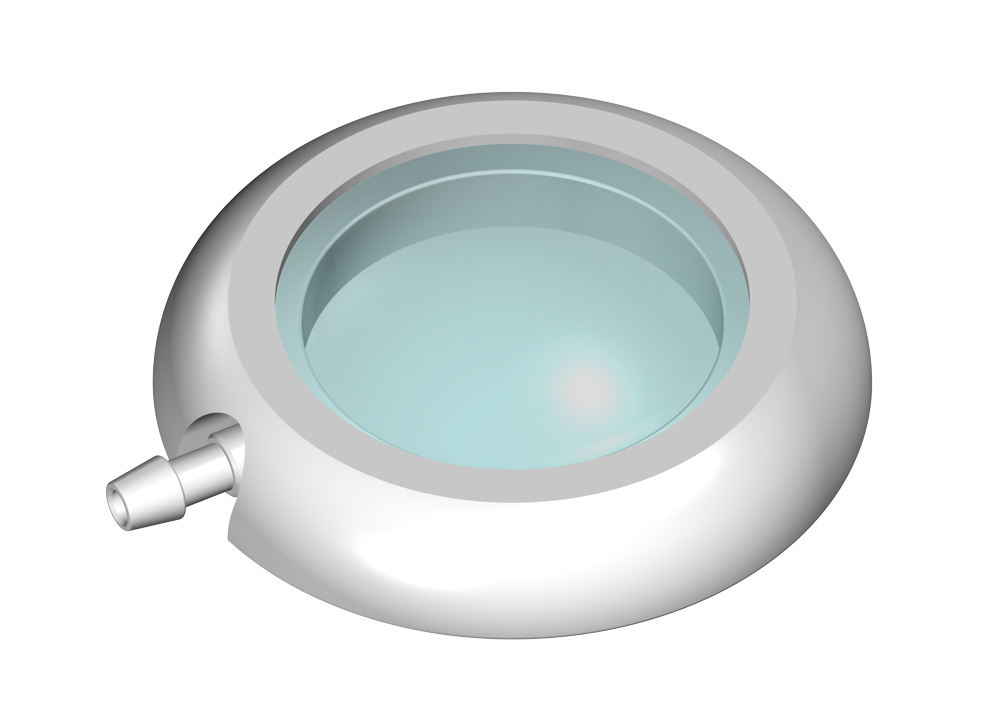

Ein solches CONTROL RESERVOIR bzw. eine Vorkammer ermöglicht die Messung des intraventrikulären Drucks, die Injizierung von Medikamenten und ggf. eine Ventilkontrolle. Eine Entnahme von Liqour und Zugabe von Medikamenten kann durch die Punktion der Silikonmembran mit einer Kanüle erfolgen. Der solide Titanboden verhindert dabei das Durchstechen mit einer Kanüle.

Alle MIETHKE CONTROL RESERVOIRE und Vorkammern sind gut erkennbar im Röntgenbild und bedingt MR sicher, d.h. Kernspinresonanzuntersuchungen (MR) oder computertomographische Untersuchungen (CT) können ohne Beeinträchtigung des Patienten durchgeführt werden.

Die Reservoire sind für Katheter mit einem Innendurchmesser von ca. 1,2 mm und einem Außendurchmesser von ca. 2,5 mm ausgelegt (außer LP-Vorkammer).